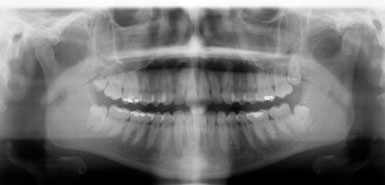

• la realització de dos radiografies intraorals (aletes de mossegada) o extraoral (ortopantomografia ) per arribar al diagnóstic més acurat.

A més, és molt important la realització de radiografies de dignòstic, tant a la primera visita com a les futures revisions, ja que el major nombre de les càries comencen als punts de contacte entre les dents o queixals, i aquests són innaccesibles visualment amb una exploració convencional.

aletadreta aletaesq   ortopanto